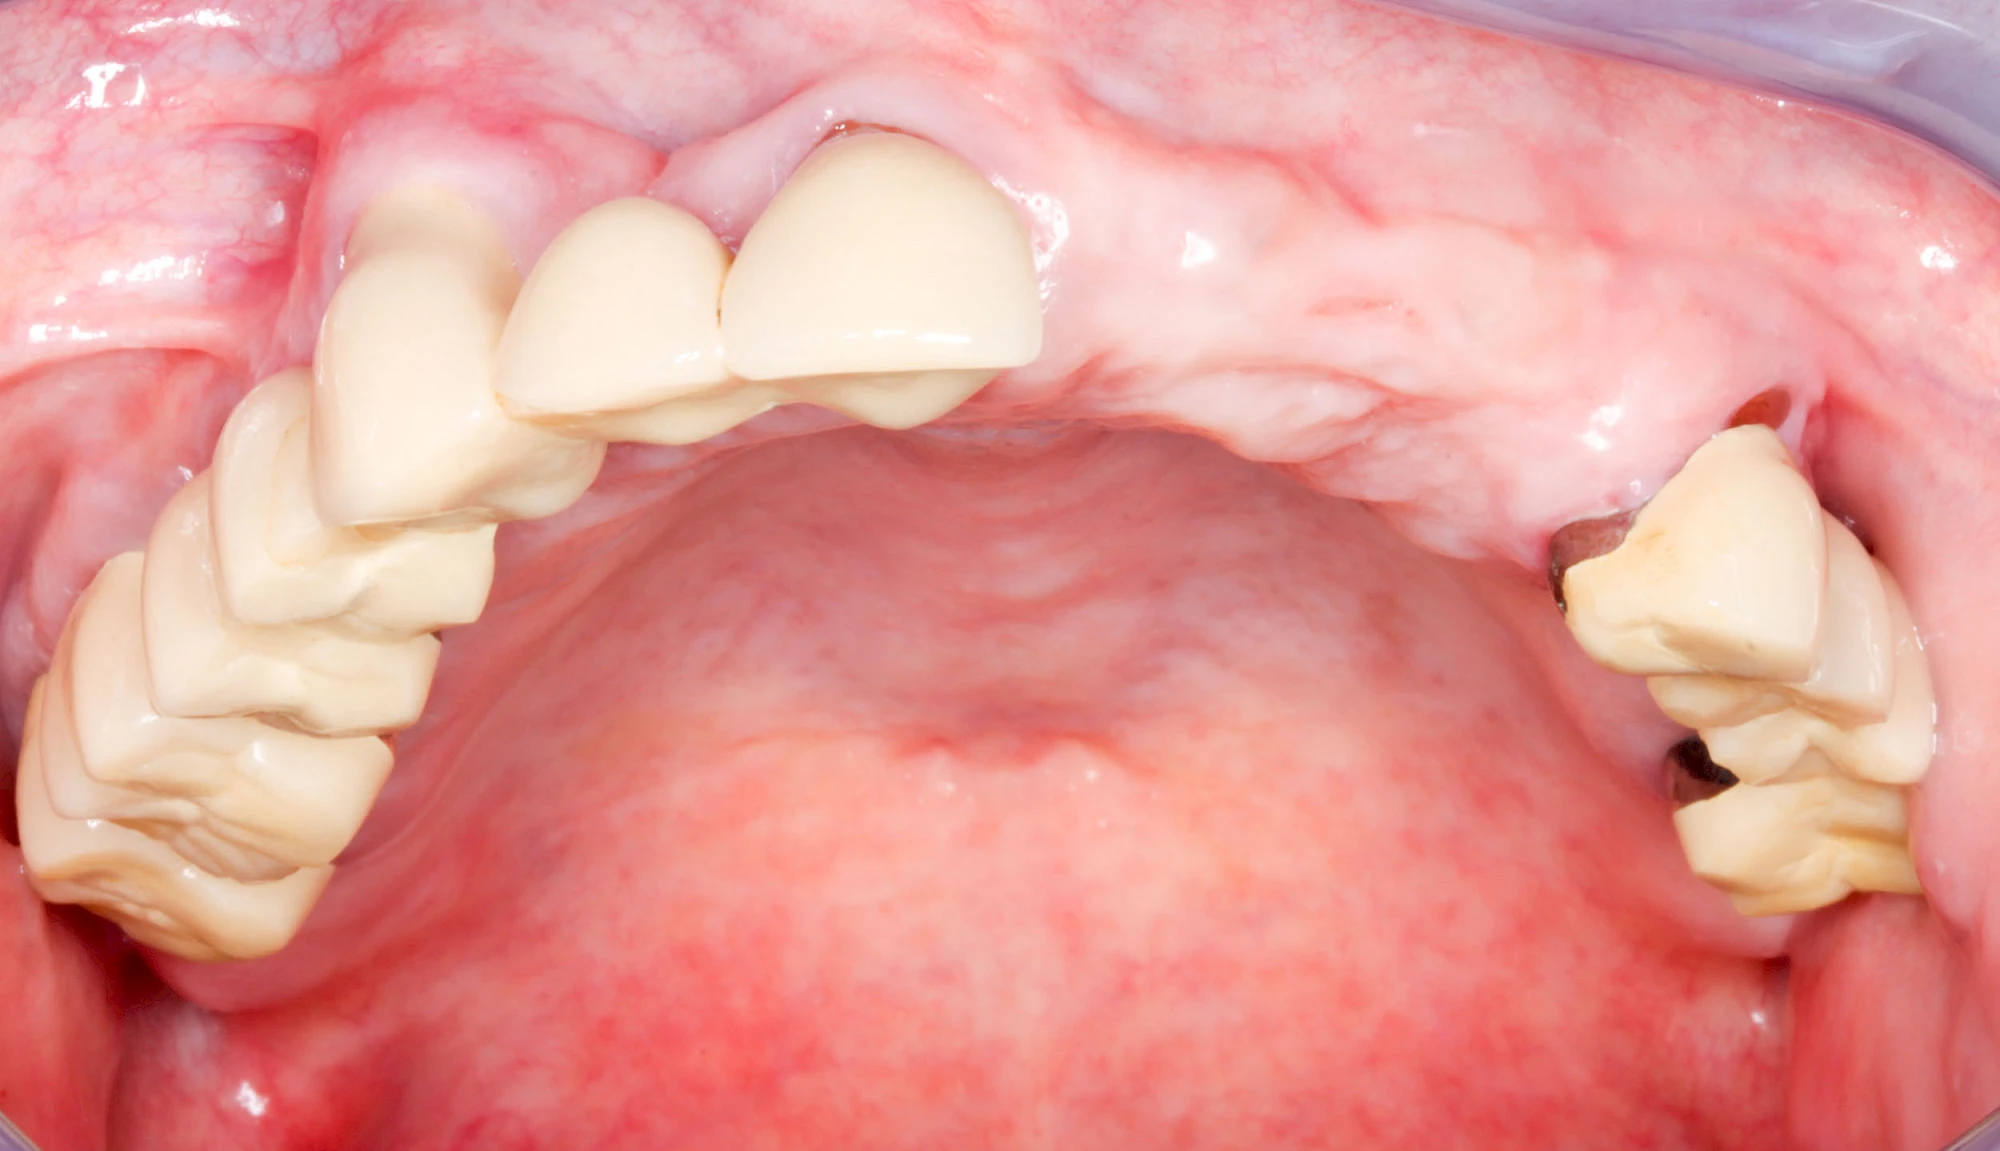

Knochenschwund (Atrophie)

Gehen die Zähne verloren, baut häufig auch der Kieferknochen ab (Knochenschwund). Die Geschwindigkeit und das Ausmaß des Knochenschwundes ist von vielen Faktoren abhängig. Neben der genetischen Veranlagung spielen auch Überbelastungen in Folge, z. B. bei ständigem Knirschen oder Pressen, eine Rolle. Auch wenn Zahnprothesen Tag und Nacht getragen werden, kann die ständige Belastung der Schleimhäute und des Knochens den Knochenschwund beschleunigen.

Aber Achtung: Manche Menschen fühlen sich ohne Zahnprothesen unwohl. Zudem kann es passieren, dass Zahnprothesen (wenn noch eigene Zähne vorhanden sind) nicht mehr passen. Dies gilt vor allem dann, wenn diese Zahnprothesen nicht nur über Nacht, sondern für einen längeren Zeitraum nicht mehr getragen werden.

Auch wenn Zahnprothesen drücken, sollten vor allem Teilprothesen jeden Tag wenigstens für ein paar Minuten getragen werden, damit sich die eigenen Zähne nicht unbeabsichtigt verstellen und die Prothese weiter passt.